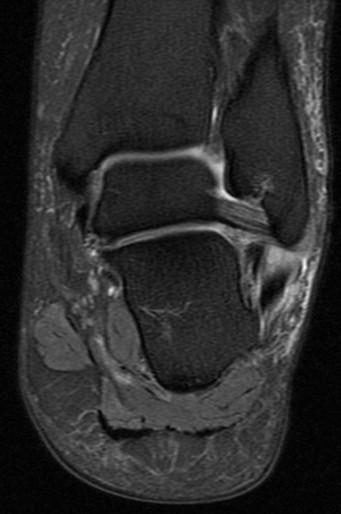

Figure 1 for case Peroneus brevis split tear

Figure 1

41 y/o avid bowler. Nice split tear from the lateral malleoulus tip down past the peroneal tubercle. Reactive tenosynovitis.

Peroneus brevis split tear